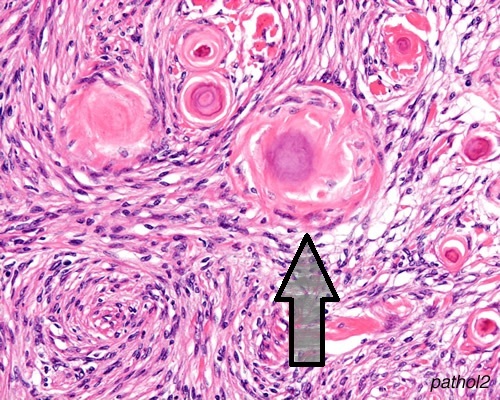

What is the indicated structure in this brain tumor biopsy? What kind of a tumor must this be?

Psammoma body; Meningioma